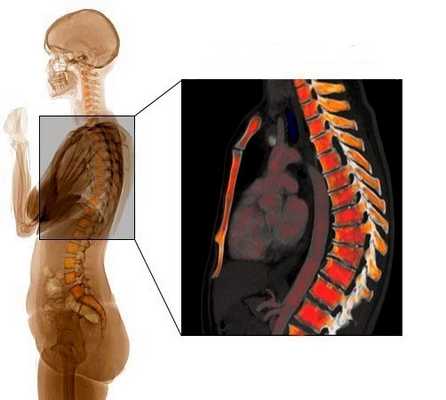

Человеческий позвоночник имеет четыре естественных изгиба: поясничный и шейный отделы изогнуты вперед (лордозы), крестцовый и грудной - назад (кифозы). Эти изгибы появились в результате приспособления к вертикальному положению тела. Они превращают позвоночник в своеобразную пружину и позволяют ему без вреда переносить разнообразные динамические и статические нагрузки. Углы изгибов в норме составляют 20-40 градусов. Позвоночник состоит из множества отдельных костей (позвонков), между которыми расположены эластичные межпозвонковые диски. Позвонки состоят из тела, дужки и отростков. Массивное тело берет на себя нагрузку, дужка участвует в образовании позвоночного канала, а отростки соединяют позвонки между собой.

В норме тела позвонков имеют почти прямоугольную форму, их задние и передние отделы примерно равны по высоте. При болезни Шейермана-Мау несколько грудных позвонков уменьшаются по высоте в передних отделах, приобретают клиновидную форму. Угол грудного изгиба увеличивается до 45-75 градусов. Спина становится круглой. Нагрузка на позвоночник перераспределяется. Ткань межпозвонкового диска «продавливает» замыкательную пластинку и выпячивается в тело ниже- или вышележащего позвонка, образуются грыжи Шморля. Связки, удерживающие позвонки, компенсаторно утолщаются, что еще больше затрудняет восстановление и дальнейший нормальный рост позвонков. Форма грудной клетки меняется, что может приводить к сдавливанию внутренних органов.

Изгибы позвоночника

Позвоночник взрослого человека имеет естественную S-образную форму. Шейный и поясничный отделы выгнуты вперед, эти изгибы называются лордозами. Грудной и крестцовый отделы выгнуты назад, эти изгибы называются кифозами. По данным Общества исследования сколиоза (Scoliosis Research Society), в норме кифотический угол в грудном отделе позвоночника составляет 20-40 градусов. Если величина кифотической дуги оказывается больше или меньше указанного значения, то в этом случае говорят о деформации позвоночника.

При болезни Шейермана происходит структурная деформация тел позвонков и позвоночника в целом. При этом заболевании кифотический угол в грудном отделе составляет около 45-75 градусов. Кроме того, происходит клиновидная деформация трех и более соседних позвонков на 5 и более градусов. Клиновидные тела позвонков определяют природу гиперкифоза, который наблюдается при болезни Шейермана. Гиперкифоз может быть скомпенсирован поясничным или шейным гиперлордозом.